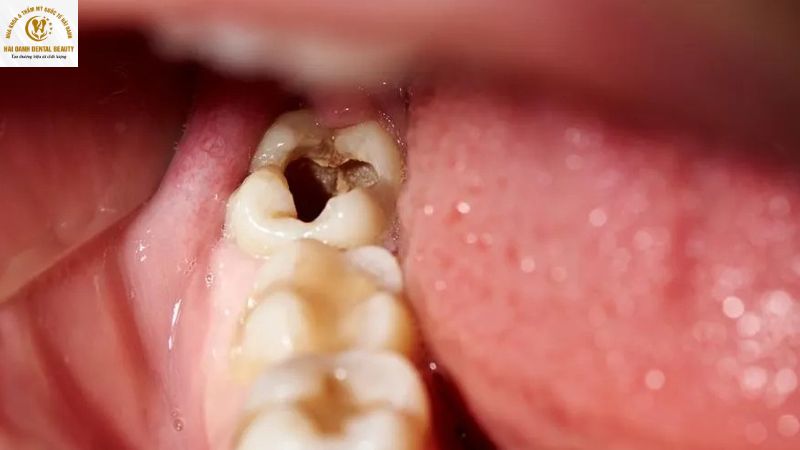

3.1. Sâu răng

Do nằm ở vị trí trong cùng của hàm, răng số 8 rất khó được làm sạch hoàn toàn sau mỗi bữa ăn. Thức ăn thừa dễ mắc kẹt, tạo môi trường lý tưởng cho vi khuẩn sinh sôi. Nguy hiểm hơn, nếu răng khôn chỉ mọc một phần hoặc mọc lệch đâm vào răng bên cạnh, nguy cơ sâu răng, viêm nhiễm tăng cao. Lâu ngày, tình trạng này có thể dẫn đến những cơn đau nhức dữ dội, ảnh hưởng nghiêm trọng đến sinh hoạt hàng ngày.

- Răng khôn có bệnh lý: Răng khôn bị sâu nặng, viêm tủy hoặc mắc các bệnh nha chu nghiêm trọng mà không thể điều trị hiệu quả.

Răng khôn bị sâu, viêm tuỷ đau ảnh hưởng đến việc ăn nhai cũng như sinh hoạt hàng ngày